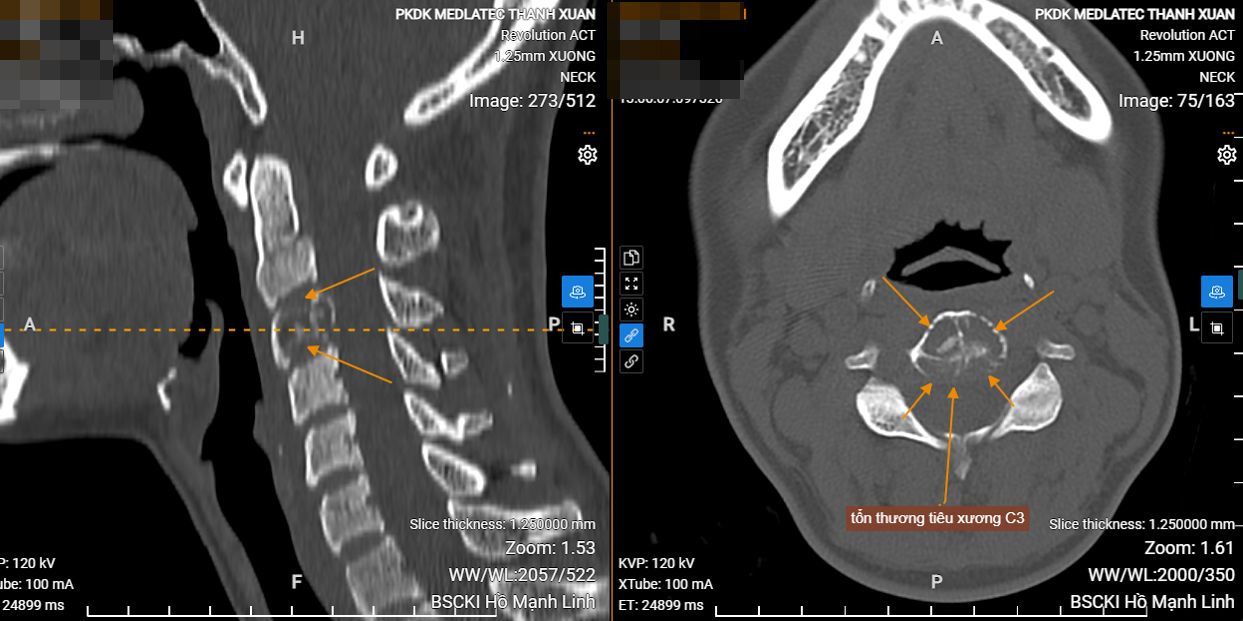

Bác sĩ CKI. Kiều Trí Lộc - Chuyên khoa Chẩn đoán hình ảnh tại Hệ thống Y tế Medlatec cho hay, sau khi thăm khám lâm sàng và phát hiện các dấu hiệu bất thường tại cột sống cổ, bệnh nhân L được chỉ định chụp cắt lớp vi tính để đánh giá chi tiết hơn. Kết quả cho thấy tổn thương tiêu xương tại thân đốt sống C3, nghi ngờ là u xương thứ phát.

Tổn thương tiêu xương tại thân đốt sống C3 của bệnh nhận ghi nhận trên hình ảnh chụp CT (ảnh: BSCC).